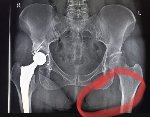

Здравствуй двачик, пишет вам простой рентгенолог из мухосранской поликлиники, сегодня я буду флексить зарплатой за ноябрь! Аж ПЯТЬДЕСЯТ ТРИ ТЫЩИ ПЕРЕВЕДУТ! С пруфом! А чего достигли вы? Ну и в доктора тож поиграем! Я буду вам картинки показывать, а вы пиздецомы находить! Найдите пиздецому на фтчк! Отчет еще по фог считать квартальный и годовой сегодня :-(